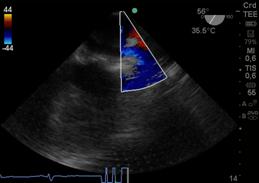

Luego con Doppler Color, analizamos la dirección del chorro regurgitante que es opuesta a la valva comprometida, el tamaño del jet regurgitante y su relación con el área de la aurícula izquierda (AI). Debemos tener en cuenta que el mapeo color del chorro regurgitante está influenciado por parámetros del ecógrafo: ganancia, PRF, límite de Nyquist, y por parámetros fisiológicos: presión arterial, volemia.

Otro factor que afecta el tamaño del chorro es la dirección de éste, los centrales en la aurícula aparecen más grandes con Doppler Color, que aquellos excéntricos que corren sobre la pared auricular, generando un efecto coanda (Figura 15), con un volumen regurgitante muy similar y que por su sola presencia le confiere severidad.

Figura 15 imagen de 4 cámaras medioesofágico con insuficiencia mitral severa, observada con Doppler color (escala 64) con efecto “coanda”, reflujo hacia la pared de AI.

Clasificamos la IM en leve si el área del jet es < 4cm2, o <20% del área de la AI; moderado de 4-8cm2 y severo mayor de 8cm2.